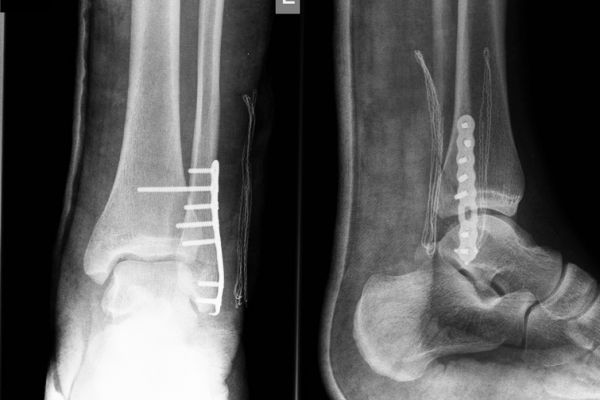

Gabinet ortopedyczny prowadzony przeze mnie specjalizuje się w leczeniu schorzeń i urazów kończyn górnych i dolnych. Zajmuję się leczeniem choroby zwyrodnieniowej stawu biodrowego i kolanowego, uszkodzeń wewnętrznych stawu kolanowego i barkowego, złamań w obrębie kończyn górnych i dolnych oraz urazów ścięgien i mięśni kończyn górnych i dolnych. Ponadto wykonuję diagnostykę USG narządu ruchu i badanie preluksacyjne (USG bioderek niemowląt). Leczę również neuropatie uciskowe kończyn (zespół kanału nadgarstka, rowka nerwu łokciowego, kanału Guyona) oraz uszkodzenia wewnętrzne stawów kończyn górnych i dolnych. Zapraszam do mojego gabinetu, gdzie dobiorę odpowiednie do schorzenia metody leczenia i zakwalifikuję do ewentualnego leczenia operacyjnego. W celu umówienia się na wizytę proszę o kontakt telefoniczny z rejestracją gabinetu ortopedycznego w Lesznie.